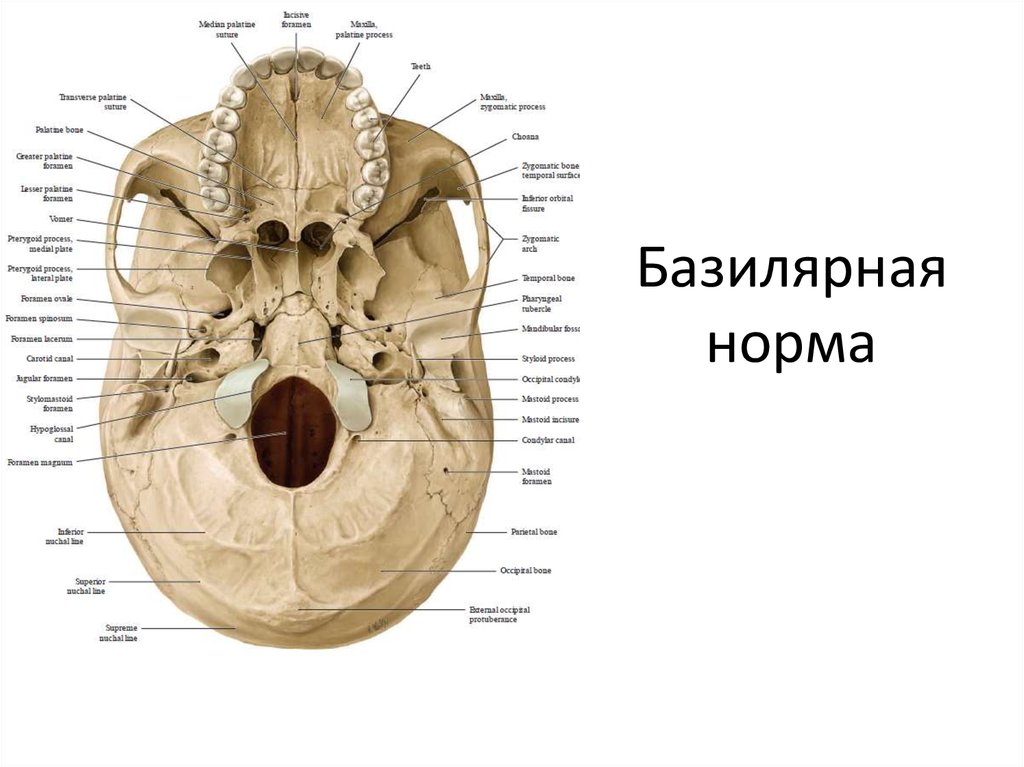

Анатомические детали: Фотографии топографии черепа с нижнего вида

Раздел: Альбом идей